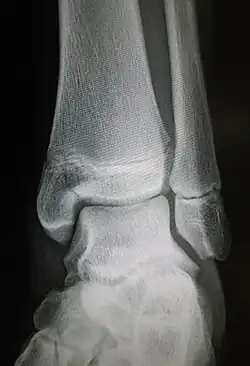

| Radiograph showing a Maisonneuve fracture of the proximal fibula | |

The Maisonneuve fracture is a spiral fracture of the proximal third of the fibula associated with a tear of the distal tibiofibular syndesmosis and the interosseous membrane. There is an associated fracture of the medial malleolus or rupture of the deep deltoid ligament of the ankle. This type of injury can be difficult to detect.[1][2]

Ankle radiographs are used to detect widening of the tibiofibular syndesmosis or medial clear space. The medial clear space is the area between the talus of the ankle and the medial malleolus. Damage to the deltoid ligament and syndesmotic ligaments result in mortise instability, causing the talus to laterally shift and widen the medial clear space.[4][12] A clinical study, conducted in 2006 and published in the Journal of Bone and Joint Surgery, found that the medial clear space size of a normal ankle and an injured ankle measured at 4 millimetres and 5.4 millimetres in length respectively.[11] To confirm diagnosis, full-leg radiographs are used to inspect for fractures of the proximal fibula and widening of the interosseous clear space (or tibiofibular clear space). The interosseous clear space is the area between the medial side of the fibula and lateral side of the tibia. A peer-reviewed study, published in Injury in 2004, found that an interosseous clear space greater than 10 millimetres indicates diastasis of the syndesmotic ligaments.[4]